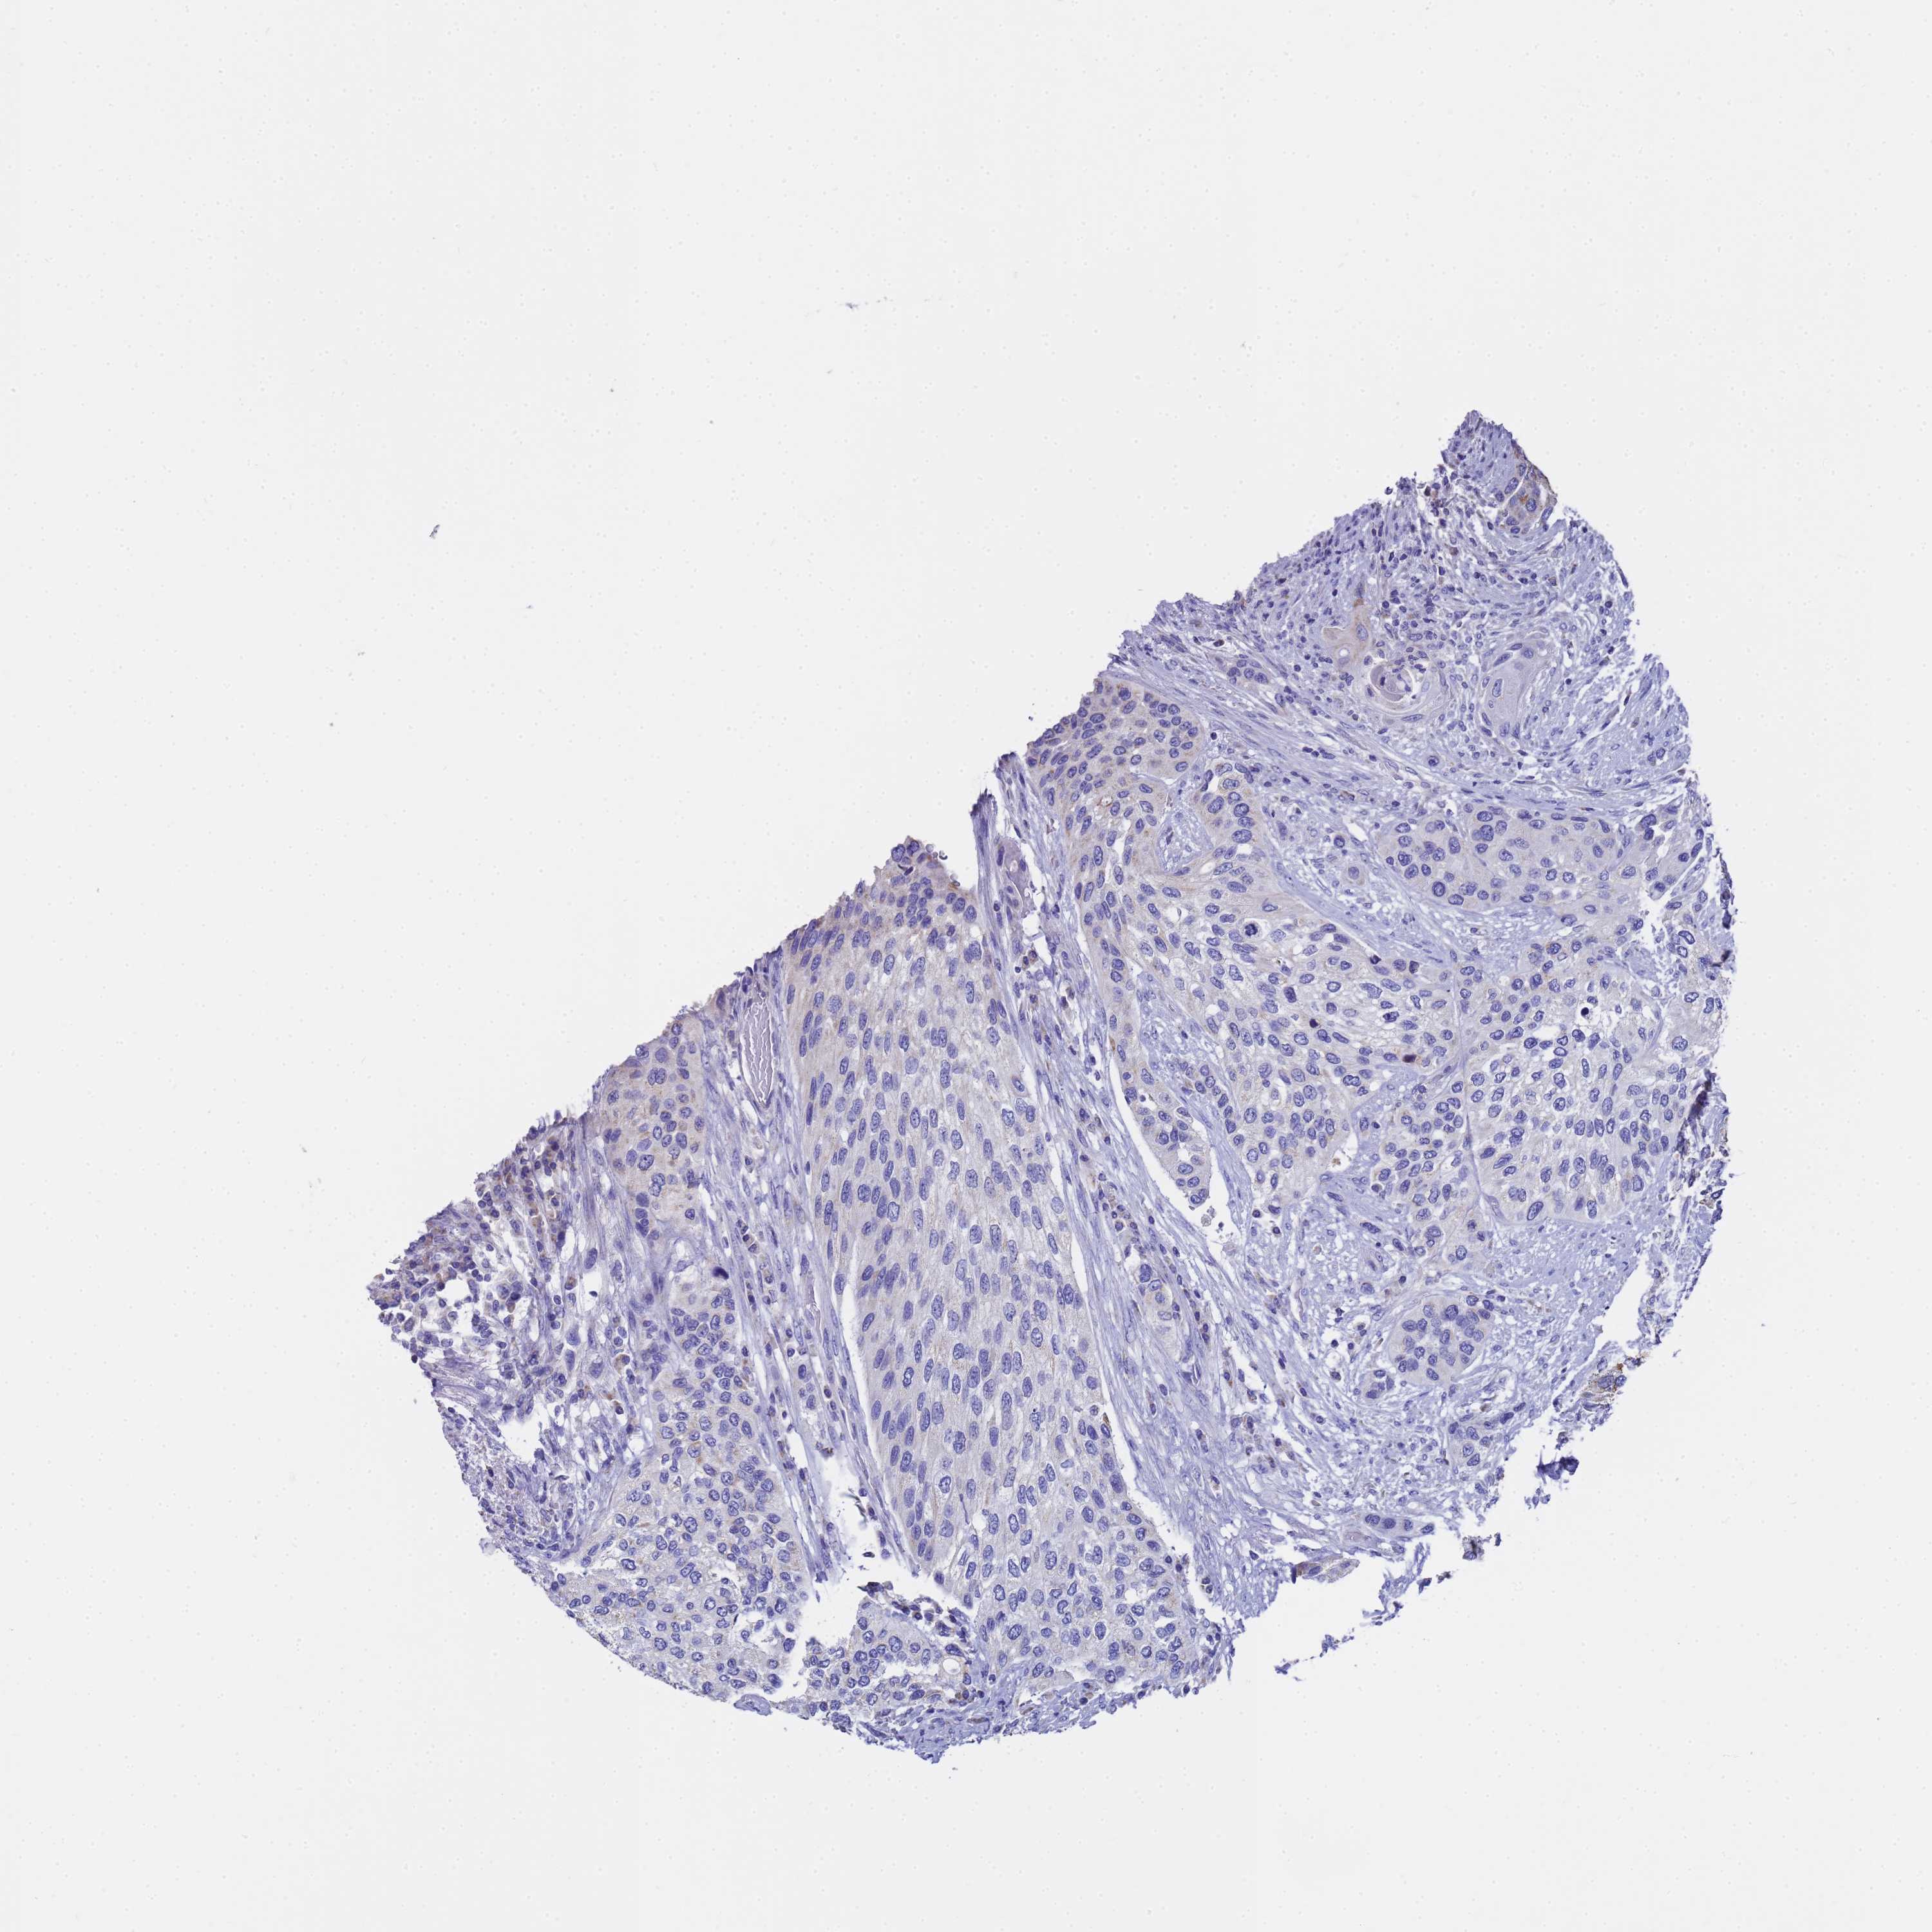

UROTHELIAL CANCER - Protein expressioni

A mouse-over function shows sample information and annotation data. Click on an image to view it in a full screen mode. Samples can be filtered based on level of antibody staining by selecting one or several of the following categories: high, medium, low and not detected. The assay and annotation is described here.

Note that samples used for immunohistochemistry by the Human Protein Atlas do not correspond to samples in the TCGA dataset.

Antibody stainingi

Antibody staining in the annotated cell types in the current human tissue is reported as not detected, low, medium, or high, based on conventional immunohistochemistry profiling in selected tissues. This score is based on the combination of the staining intensity and fraction of stained cells.

Each image is clickable and will lead to virtual microscopy that enables deeper exploration of all samples and also displays staining intensity scores, fraction scores and subcellular localization as well as patient and tissue information for each sample.

Antibody HPA046775

Antibody HPA050633

Staining

High

Medium

Low

Not detected

Intensity

Strong

Moderate

Weak

Negative

Quantity

>75%

75%-25%

<25%

None

Location

Nuclear

Cytoplasmic/membranous

Cytoplasmic/membranous,nuclear

Urothelial carcinoma, High grade

Urothelial carcinoma, Low grade

Urothelial carcinoma, NOS